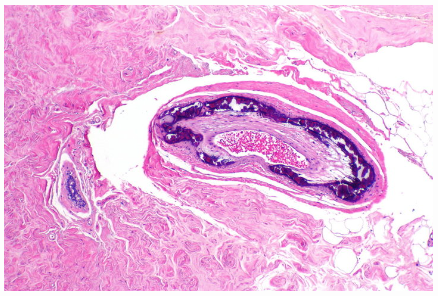

What type of arteriolosclerosis is demonstrated in the image below? _____